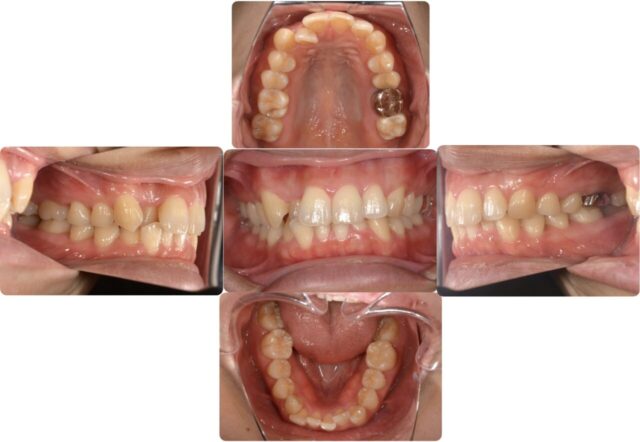

ではそれを踏まえた上でこの方の下からのかみ合わせを見てみましょう。

右側の歯のガイドが少ないですね、ということは左の奥歯に負担がかかるかみ合わせになってしまっています。

しっかりとアンテリアガイダンスを獲得できましたね!これで左側にかかっていた負荷を取り除けたので、残りの感染根管治療を行っていきます!